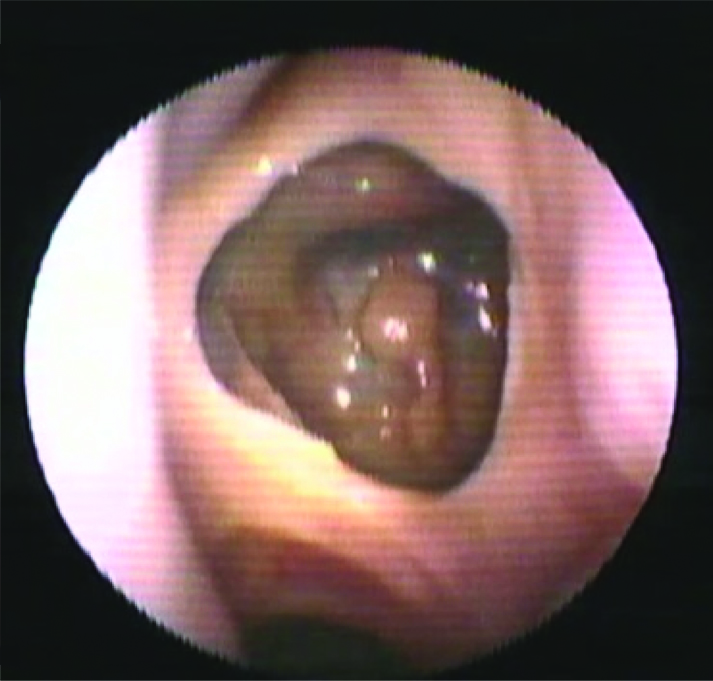

ВВЕДЕНИЕ В настоящее время в связи с распространением лучевых (МРТ, КТ) и визуальных (эндоскопия) методов диагностики наблюдается увеличение количества случаев изолированного сфеноидита [1, 2, 3]. Удельный вес изолированного сфеноидита в общей структуре заболеваний околоносовых пазух (ОНП), по данным литературы, составляет не более 5% [4, 5, 6]. Однако абсолютные цифры с учетом огромного количества случаев воспалительной патологии ОНП могут быть весьма значительными. В структуре синуситов все больше резистентных (устойчивых к лечению) форм, в том числе грибковых [7]. Данные о распространенности патологии весьма скудные, в структуре статистической отчетности стационаров и поликлиник сфеноидит как самостоятельная нозологическая форма отражается крайне редко. В то же время относительно невысокая распространенность нередко обусловливает пассивную позицию специалистов при дифференциальной диагностике поражений клиновидной пазухи (КП). Основное место в дифференциальной диагностике у данной группы пациентов занимают компьютерная томография (КТ) и магнитно-резонансная томография (МРТ). Однако трактовка результатов исследований не всегда однозначна и может приводить как к гипердиагностике, так и, наоборот, к гиподиагностике сфеноидита, выражающейся в недооценке данных лучевой диагностики и обьективной картины и нередко приводящей к развитию хронических и осложненных форм. Пациенты направляются к лор-врачу только после длительного, безуспешного лечения у специалистов смежных специальностей, что влечет высокий уровень гиподиагностики сфеноидита и наличие осложненных форм [8]. Дифференциальная диагностика патологического процесса в пазухе на дооперационном этапе чрезвычайно важна, поскольку необдуманное вмешательство может вызвать тяжелые и даже фатальные осложнения [9, 10]. От 5% до 30% всех изолированных поражений клиновидной пазухи составляют пациенты с неинвазивной грибковой формой [11, 12]. Для хронического сфеноидита характерно латентное (скрытое) течение, которое не всегда диагностируется на ранних стадиях [13, 14]. По данным ряда исследователей, частота патологических находок в клиновидной пазухе при аутопсии лиц, прижизненный диагноз «сфеноидит» у которых не был установлен, составляет от 10% до 68% [15, 16]. Очень важно изучение вопросов ремоделирования в клиновидной пазухе, в том числе явлений остеита при грибковых формах [17]. Осложненное течение изолированного сфеноиди-та - нередкое явление, при этом основным фактором развития осложнений является несвоевременная диагностика. Наиболее часто встречаются осложнения, связанные с вовлечением в патологический процесс глазодвигательных нервов, в особенности VI пары - n. abducens [4, 9, 16]. В литературе можно встретить наблюдения инвазивных, генерализованных форм грибкового сфеноидита с быстрым развитием офтальмологических, интракраниальных и системных (септических) осложнений [7, 12, 14]. Тактика лечения при изолированных поражениях клиновидной пазухи, по данным литературы, различная. Часть авторов считает наличие изолированного сфеноидита, особенно грибковых форм, мукоцеле, абсолютным показанием к операции. Другие авторы при отсутствии осложнений начинают с консервативной терапии [1, 3, 11, 12]. Задачей хирургического лечения у таких пациентов является не только купирование воспалительного процесса, но и создание условий для адекватной вентиляции пазух и предотвращения возможного рецидива. В то же время вопросы дифференцированного подхода к хирургическому лечению недостаточно освещены в научной литературе и носят преимущественно описательный характер. ш ЦЕЛЬ Провести анализ случаев изолированного поражения клиновидной пазух и выявить основные особенности и ошибки при дифференциальной диагностике на догоспитальном этапе. ш МАТЕРИАЛ И МЕТОДЫ В работе приведены данные о лечении 58 пациентов с изолированным поражением клиновидной пазухи, которые находились на стационарном лечении в ГБУЗ НОКБ им. Н.А. Семашко (кафедра болезней уха, горла и носа ФГБОУ ВО «ПИМУ» Минздрава РФ) в период 2015-2018 гг. Возраст пациентов - от 18 до 68 лет. Средний возраст пациентов с изолированным сфеноидитом составил 43 года, среди них превалировали женщины до 35 лет. Гендерное распределение было следующее: мужчины - 21 (30,7 %), женщины - 37 (69,3%). Давность заболевания составила 26±19 дней. Всего в клинике в данный период наблюдались 118 пациентов с различными формами поражения клиновидной пазухи, у 60 пациентов поражение КП наблюдалось как проявление хронического риносинусита (с полипами и без), то есть имело место сочетанное поражение нескольких или всех околоносовых пазух, и данные наблюдения не были включены в исследование. Критерии включения в исследование: рентгенологические (КТ, МРТ) признаки патологического процесса в клиновидной пазухе, специфическая и неспецифическая симптоматика, латентное течение сфеноидита, отсутствие патологического процесса в других околоносовых пазухах. Критерии исключения: сочетанное поражение других групп околоносовых пазух, нозокомиальный сфенои-дит. Такие состояния, как искривление носовой перегородки, вазомоторный/аллергический ринит, гипертрофия носовых раковин, mnchabullosa средних носовых раковин критериями исключения не являлись. Пациенты с впервые установленным диагнозом составили 85% от общего числа, 15% наблюдений - рецидивные формы заболевания, в том числе 5 пациентов были после ранее проведенного оперативного вмешательства (таблица 1). Морфологическая форма Количество наблюдений Полипозный процесс 15 (25,8%) Киста 18 (31%) Мукоцеле 5 (8,6%) Грибковый сфеноидит 12 (20,6%) Инвазивный грибковый сфеноидит 2 (3,4%) Менингоцеле 4 (6,8%) Новообразование 2 (3,4%) Таблица1. Распределение по виду патологического процесса Table 1. Distribution by the type of pathological process При поступлении в стационар проведено обследование пациентов в следующем объеме: клинические анализы, консультации смежных специалистов - невролога, нейрохирурга, офтальмолога (в зависимости от клинических проявлений). Всем пациентам проводилась предоперационная эндориноскопия. При подготовке к оперативному лечению оценивалось наличие у пациента сопутствующих заболеваний, течение которых проявляется симптоматикой со стороны ОНП и может в значительной степени оказывать влияние на течение патологического процесса в полости носа и ОНП: бронхиальная астма, аспириновая триада, персистирующий или интермиттирующий аллергический ринит, а также комбинация данных заболеваний. ш ОБСУЖДЕНИЕ И РЕЗУЛЬТАТЫ В большинстве случаев причиной обращения за помощью был цефалгический синдром. Все пациенты с болевым синдромом первоначально проходили обследование у невролога либо терапевта, им выполнялось МРТ-исследование на догоспитальном этапе. В данной группе пациентов (n=21, 36,2%) 9 человек были направлены к оториноларингологу сразу после получения данных МРТ. 12 пациентов проходили дальнейшее консервативное лечение у невролога либо не получали никакого лечения, несмотря на очевидные данные МРТ-исследования. После МРТ-исследования уточняющее КТ-исследование было назначено только 3 пациентам. Остальные пациенты были направлены в стационар с результатами МРТ. Таким образом, в рамках нашего исследования можно говорить о превалировании МРТ-диагностики в догоспитальном обследовании и игнорировании специалистами КТ-исследования. Симптоматическая картина у исследуемых пациентов весьма вариабельна: от латентных бессимптомных форм до тяжелых цефалгических и офтальмологических проявлений. Мы наблюдали определенную взаимосвязь между симптоматическими проявлениями и морфологической формой заболевания (таблица 2). В целом манифестирующая ринологическая симптоматика наблюдалась не более чем в трети наблюдений. В остальных ситуациях мы наблюдали либо неспецифическую симптоматику (цефалгические и/ или офтальмоплегические проявления), либо бессимптомное течение. Латентные формы поражений КП, когда патологический процесс выявлен случайно при МРТ/КТ-обследовании по другим причинам, составили около 20% от всех наблюдений. Чаще всего это были поражения в виде кисты клиновидной пазухи и мукоцеле (рисунок 1), реже бессимптомное течение наблюдалось при грибковой форме поражения и менингоцеле (рисунки 2, 3). Хирургическое лечение. Всем пациентам проводилось хирургическое лечение, после тщательного анализа КТ-томограмм для уточнения варианта строения клиновидной пазухи и наличия анатомических вариантов строения (клетки Оноди, дигисценции канала внутренней сонной артерии, зрительного нерва и т.д.) (рисунки 4а, 4б). Все оперативные вмешательства выполнялись под общим обезболиванием. Применялись следующие доступы: трансназальный, расширенный трансназальный, трансэтмоидальный, доступ по методике Bolger Box, транскрыловидный (в одном случае) (таблица 3, фото 5, 6). Расширенный доступ (Wormald PJ. 2005, Palmer J.N. 2013) в отличие от традиционного с механическим расширением естественного соустья подразумевает выкраивание короткого (5-10 мм) назосептального лоскута Морфологическая форма Клинические симптомы Головная боль Постназальный затек Голово кружение Назальная обструкция Глазничные симптомы Полипозный процесс/ полипозно-гнойный + +++ - ++ - Киста - - - + - Мукоцеле ++ + - + - Грибковый сфеноидит ++ ++ + + + Инвазивный грибковый сфеноидит +++ ++ + + +++ Менингоцеле + + + - - Новообразование ++ + + - +++ «+» - степень выраженности симптома от + до +++. «-» - отсутствие симптома. Таблица 2. Симптоматические проявления Table 2. The symptomatic manifestation Рисунок 1. Мукоцеле клиновидной пазухи. Figure 1. Mucocele of the sphenoid sinus. Рисунок 2. Грибковый сфеноидит. 2.1 КТ (аксиальный срез); 2.2 Соустье обтурировано полипом. Трансназальный доступ; 2.3 - грибковые массы в пазухе. Figure 2. Fungal sphenoiditis. 2.1 CT (axial cross-section); 2.2 Anastomosis is obturated by a polyp. Transnasal access; 2.3 - fungal masses in the sinus. Рисунок 3. КТ (фронтальный срез). Остеит стенок клиновидной пазухи при грибковом синусите. Figure 3. CT (front section). Osteitis of the walls of the sphenoid sinus in fungal sinusitis. Рисунок 4а. Дигисценция канала внутренней сонной артерии. КТ-исследование. Figure 4a. Dehiscence of the internal carotid artery channel. CT study Рисунок 4б. Дигисценция канала внутренней сонной артерии. Эндоскопическая картина. Figure 4b. Dehiscence of the internal carotid artery channel. Endoscopic image. Таблица 3. Виды хирургических вмешательств Table 3. Types of surgical interventions слизистои ниже и медиальнее соустья пазухи на ножке с питанием от заднеИ септальноИ ветви крылонебной артерии с широким обнажением и резекцией передней стенки пазухи. При этом соустье мы расширяли при помощи бора. Данный способ упрощает задачу в том случае, если естественное соустье не визуализируется и технически не доступно и/или есть необходимость широкого открытия пазухи. Лоскут на питающей ножке используется для закрытия широкого костного дефекта, что способствует его дальнейшей эпите-лизации и минимизирует развитие в последующем остеита. Исследования ряда авторов свидетельствуют о том, что трансэтмоидальный и трансназальный доступ могут с одинаковым успехом применяться при Рисунок 5. 5a - грибковое тело латерального кармана клиновидной пазухи (КТ, аксиальный срез); 5b - расширенный трансназальный доступ (700 эндоскоп); 5c - КТ через 6 мес. после операции. Figure 5. 5a - fungal ball in the lateral “pocket" of the sphenoid sinus (CT, axial section); 5b - extended transnasal access (700 endoscope); 5c - CT in 6 months after operation. Рисунок 6. Менингоцеле клиновидной пазухи. 6а - МРТ (фронтальный срез); 6b - расширенный трансназальный доступ. Пластика ликворного дефекта после удаления менингоцеле (материал - жир). Figure 6. Meningocele of the sphenoid sinus. 6a - MRI (frontal section); 6b - extended transnasal access. Plasty of the liquor defect after the meningocele removal (the material - fat). Рисунок 7. Соустье через 1 год после расширенного доступа. Figure 7. Anastomosis 1 year after expanded access. Рисунок 8. Соустье через 3 года после расширенного трансназального доступа. Рисунок 9. Рецидив полипозно-гнойного сфеноидита через 6 месяцев после операции. причиной рецидива патологического процесса и потребовал проведения ревизионного вмешательства. В одном случае у пациента, которому ранее выполнена сфенотомия по поводу хронического сфеноидита, но не была вскрыта (распознана) клетка Оноди, в которой локализовалось грибковое воспаление, также потребовалась повторная операция. Figure 9. Recurrence of polypous-purulent sphenoiditis in 6 months after surgery. Figure 8. Anastomosis 3 years after expanded access. изолированном поражении пазухи. Трансназальный доступ более безопасен, чем трансэтмоидальный, и является методом выбора при изолированном поражении пазухи при условии, что патологический процесс в пазухе не требует широкой ревизии и/или создания достаточного по объему сообщения в тех ситуациях, когда велик риск рецидива. Осложнений в послеоперационном периоде не наблюдалось. На 5-7 сутки всем пациентам выполнялась эндориноскопия. В срок от 2 до 3 месяцев 11 пациентам выполнено контрольное КТ. Остальные пациенты (из отдаленных районов) не проходили контрольного осмотра. При выполнении расширенного доступа удалось добиться формирования стойкого, эпителизи-рованного соустья во всех случаях (рисунки 7, 8). При полипозно-гнойных формах сфеноидита наиболее часто наблюдались рецидивы заболевания, однако здесь требовалась только противовоспалительная терапия, в том числе орошение пазухи через сформированное соустье (рисунок 9). Частота развития спаечного процесса после вмешательств составила около 20%, при этом только в 3 наблюдениях рубцово-спаечный процесс явился ш ВЫВОДЫ Изолированный сфенои-дит в структуре пациентов, которым проводилось эндохирургическое лечение при патологии ОНП, составил 3% (около 30% от общего числа сфеноидитов). В стационаре пациенты с точно установленным диагнозом «изолированный сфеноидит» на догоспитальном этапе составили не более 12% от общего числа, что связано как с гиподиагностикой, пассивной позицией в отношении патологии клиновидной пазухи у врачей амбулаторного звена, так и с тактическими ошибками. Отмечено превалирование МРТ-диагностики в догоспитальном обследовании и игнорирование специалистами КТ-исследования. Основной метод лечения изолированного сфеноидита - хирургический. Наиболее часто применялся расширенный трансназальный доступ. Необходимо сочетание с медикаментозным лечением в послеоперационном периоде. Требуются дальнейшие исследования с целью изучения особенности/безопасности и клинической эффективности различных эндохирургических доступов. W Конфликт интересов: все авторы заявляют об отсутствии конфликта интересов, требующего раскрытия в данной статье.Об авторах